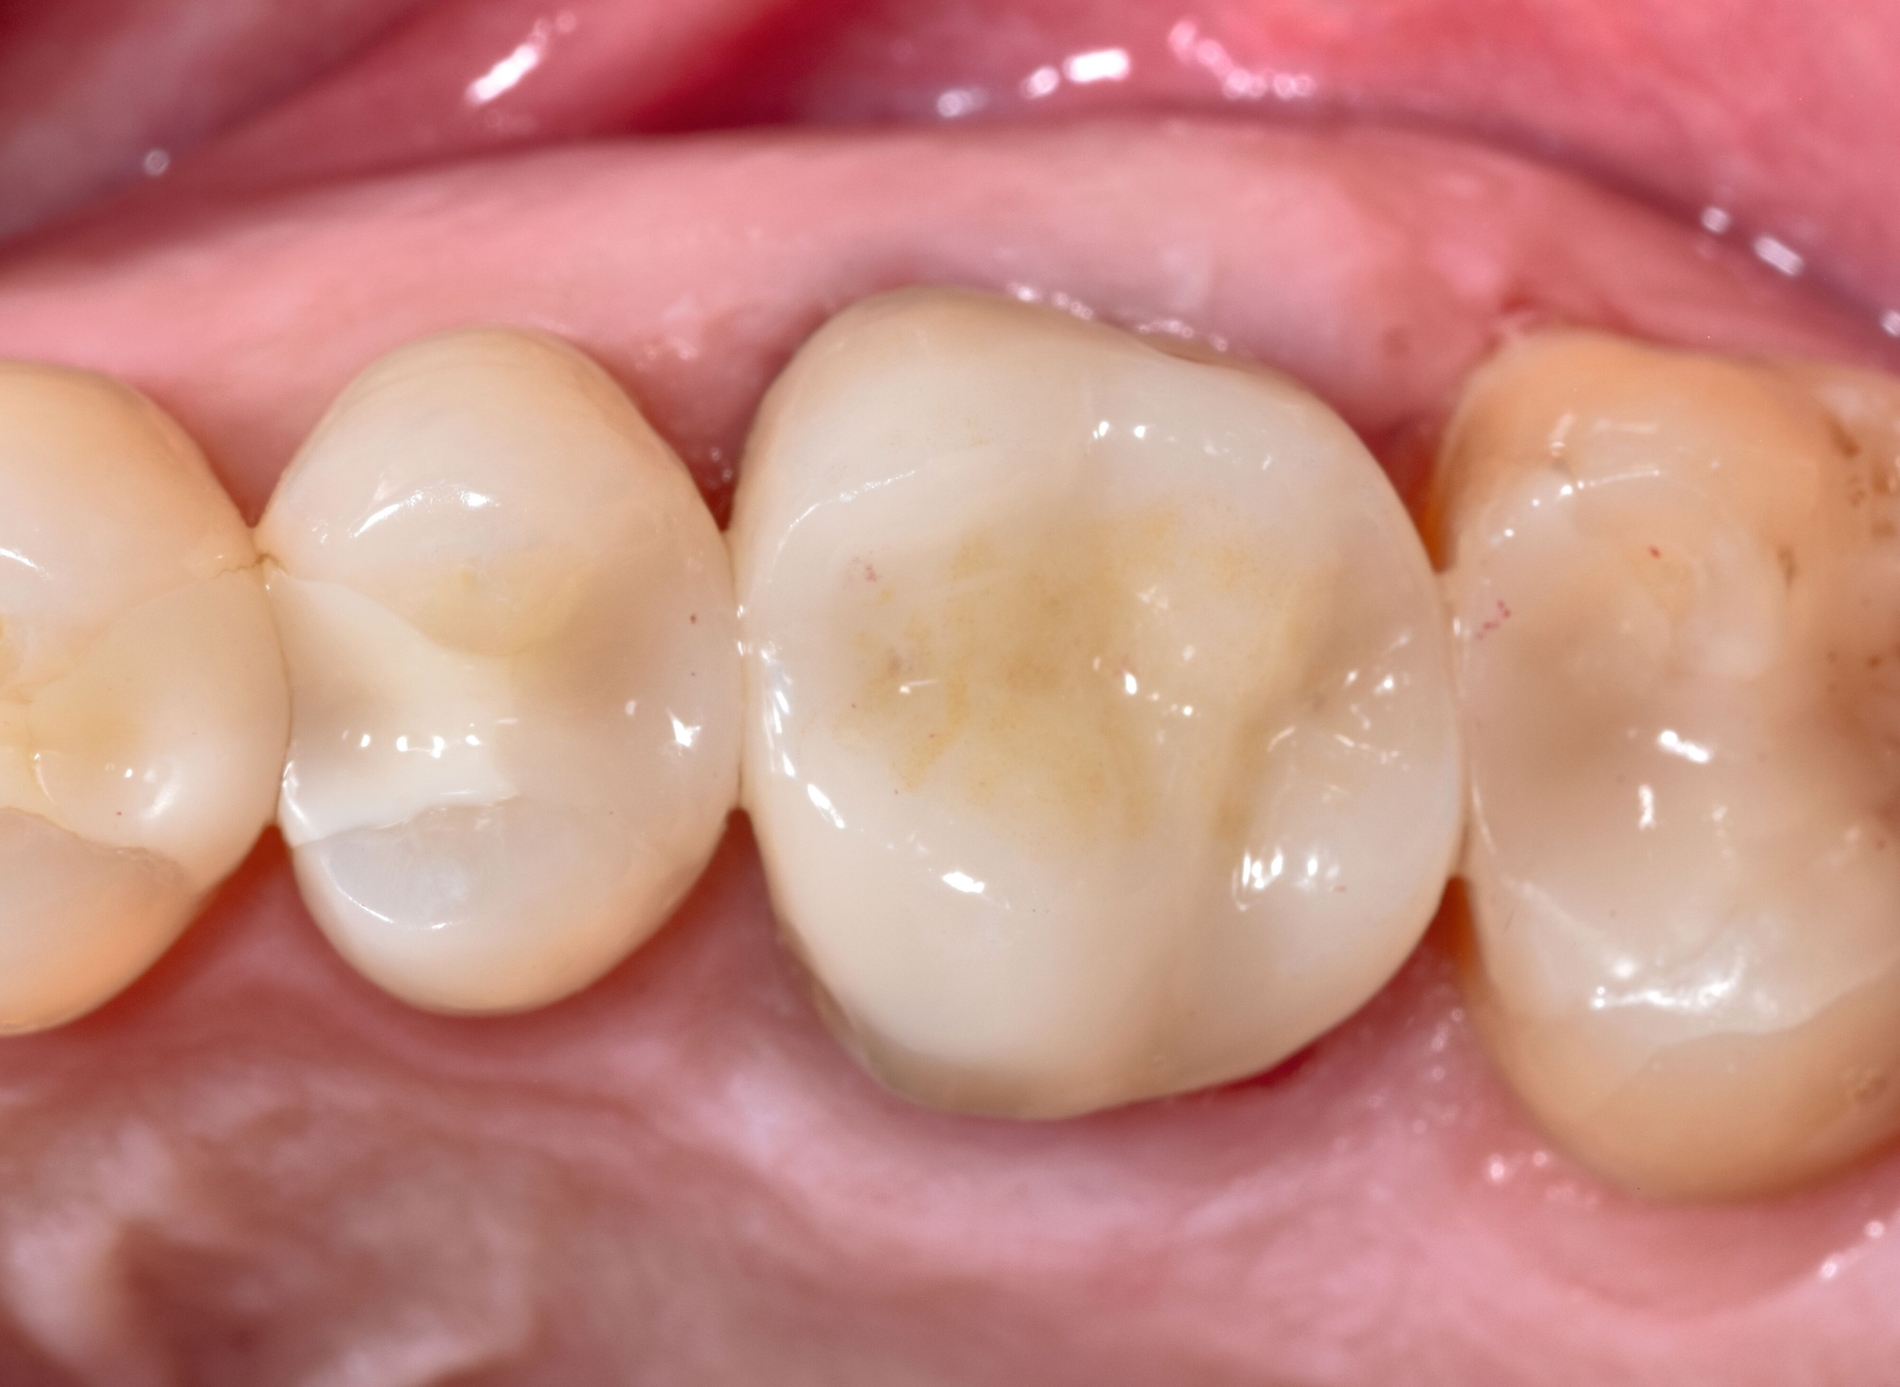

Im weiteren Restaurationsverlauf erfolgen zunächst eine Nachpräparation und das Finieren des Zahnes 26, anschließend die optische Abformung für die Herstellung einer Teilkrone aus Lithium-Disilikat-Glaskeramik (siehe Materialliste). Nach Anprobe der indirekten CAD/CAM-Restauration wird die Restauration gereinigt und für 20 s mit Flusssäure angeätzt, mit einem speziellen MDP-haltigen Primer bestrichen und in einem Lichtschutzgefäß gelagert. Nach Trockenlegung und Reinigung wird der Zahn 26 angeätzt, ein Adhäsiv aufgetragen, die Deckrestauration mit Befestigungskomposit bestrichen und adhäsiv befestigt (Abbildung 3, Materialliste).

Je nach Befestigungsmaterial kann vor der Lichtpolymerisation ein Glycerin-Gel auf den Zementspalt aufgetragen werden. Nach Lichthärtung von allen Seiten werden die Überschüsse entfernt, die Okklusion wird eingeschliffen und die Restauration abschließend poliert. Es finden zudem eine Anpassung von Interdentalraumbürsten sowie eine Mundhygieneinstruktion statt. Darüber hinaus wird die Patientin über notwendige regelmäßige Kontrollen im Sinne der präventiven Erhaltungstherapie aufgeklärt.

Bei der Kontrolle nach sechs Monaten zeigen sich an Zahn 26 entzündungsfreie Verhältnisse und kein Anhalt auf Lockerung oder erhöhte Sondierungstiefen. Die Patientin verwendet täglich eine Interdentalraumbürste als Hilfsmittel zur häuslichen Mundhygiene. Zur Kontrolle wird ein Zahnfilm angefertigt. Röntgenografisch zeigt sich im distalen Bereich des Zahnes 26 die Kastenelevation aus Komposit mit stufenlosem Übergang zur indirekten keramischen Deckrestauration (Abbildung 4).